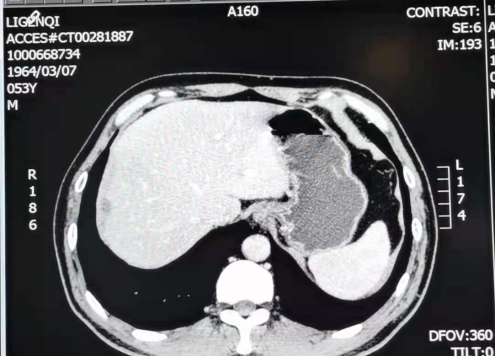

2018-07-24 复查CT

肝边缘部见多发低密度结节,边界清楚,大者约2.1cm×l.9cm,未见强化,体积较前增大,数量较前略增多;肝脏边缘结节,体积较前增大,数量较前略增多,提示腹膜种植转移。

2018-07-24 肝MRI:

1.肝S4-8段边缘处多发结节,与前片(2018-05-25)比较,部分体积较前略增大,考虑转移瘤较不典型血管瘤可能性大,建议随访;2.肝S5、S6小结节,转移待排,建议随访。